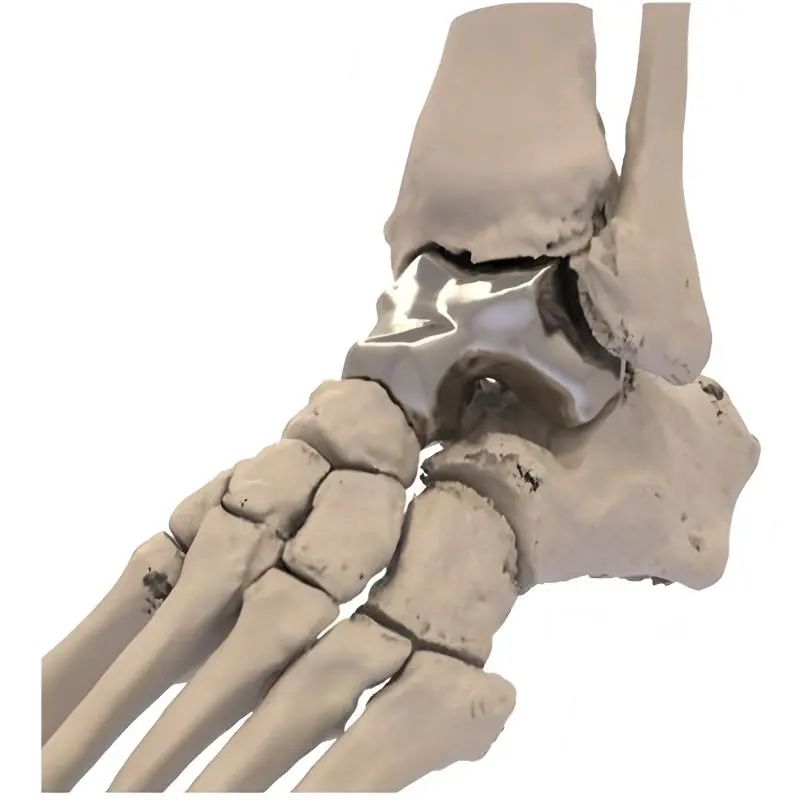

“我们通过3D建模技术,对患者的距骨进行1:1数字化复刻,结合生物力学分析精准计算骨骼的生理曲度、受力点等参数,最终定制出与患者结构完美契合的专属假体。”江川区医共体总医院骨科主任杨勇介绍说,作为人体足部的“承重枢纽”,距骨承担着缓冲震荡、维持平衡的关键功能,一旦发生严重坏死或损伤,传统治疗手段往往面临假体适配难、术后恢复差等困境。尤其是传统的距骨假体往往是标准化生产,难以满足每个患者的个性化需求。而3D 打印的假体能够精准匹配患者的骨骼结构,大大减少了手术过程中对周围组织的损伤,同时也提高了假体的稳定性和使用寿命。

今年1月,在云南省第一人民医院专家团队的全程指导与紧密协作下,江川区医共体总医院骨科团队凭借精湛技艺,将经过精密打印、毫米级误差校准的全距骨假体,稳稳植入到郑阿姨体内。